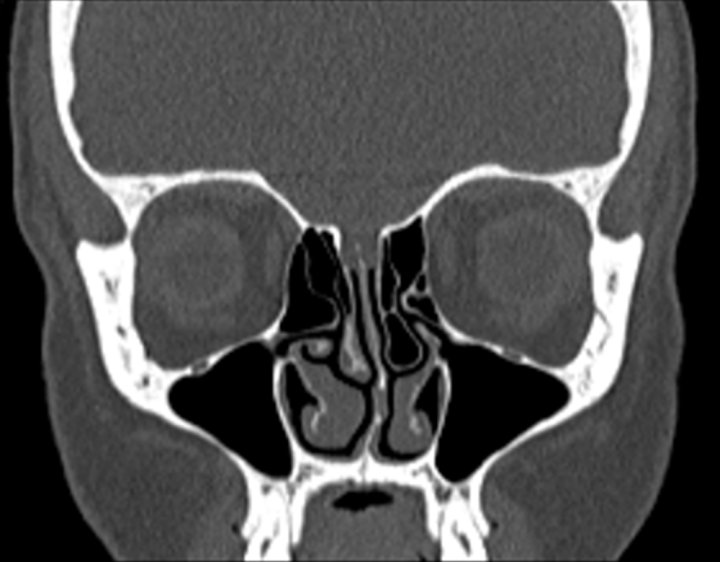

Click any image for labels.